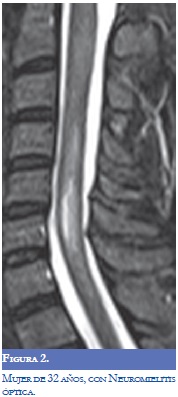

La Neuromielitis Óptica (NMO) se ha relacionado con la EM y el LES, en la actualidad se considera una entidad separada de la EM con patogénesis diferente que predomina en el sexo femenino. Se encuentra una reactividad mediada por la inmunoglobulina del tipo G contra su principal antígeno identificado la acuaporina-4 (AQP-4). La NMO se puede manifestar en forma agresiva en el LES (1-3). Jarius y colaboradores informaron frecuencias altas de anticuerpos AQP-4 en pacientes con enfermedades del tejido conectivo y cuando se evaluaron los pacientes con LES o síndrome de Sjögren con clínica de neuritis óptica o mielitis los títulos de AQP-4 fueron altos. El mecanismo determinante de la asociación con LES o Síndrome de Sjögren en la EM sigue sin resolverse pero con los datos actuales se recomienda valorar la presencia de anticuerpos AQP-4 en los pacientes que llenen criterios para la NMO (8,9). La EM puede tener anticuerpos antifosfolípidos positivos y manifestarse con NMO y la neuritis óptica asociada con LES y SAF suele ser unilateral al contrario de la EM en la cual puede ser bilateral (2,3).

El LES con mielitis transversa tiene una mayor prevalencia de anticuerpos antifosfolípidos que en los casos de LES sin mielitis transversa. La "mielitis longitudinal" principalmente cervical y torácica que describe el compromiso continuo multinivel se presenta principalmente en pacientes con LES (1,2). La mielitis en la EM afecta usualmente un nivel o de manera alterna varios niveles.

La RM (Figuras 1-4) permite valorar mejor la sustancia blanca cerebral y se pueden ver lesiones pequeñas de causas isquémicas que se presentan en el LES/SAF hasta en 30 a 70% y se asemejan a las placas desmielinizantes de la EM (2). El concepto de realce con gadolinio que sugiere inflamación no es específico para la EM, los complejos inmunes inducen la alteración de la barrera hematoencefálica, de modo que la RM como método diagnóstico no permite definir la causa. La distribución de las lesiones pueden orientar al diagnóstico y las lesiones subcorticales prevalecen en el LES/SAF y las periventriculares próximas al cuerpo calloso como lesiones ovoides (dedos de Dawson) y los hoyos negros son característicos de la EM. La evolución de las lesiones en diferentes secuencias de RM es de ayuda para la diferenciación y se consideran de evolución dinámica en la EM y en cambio permanecen estáticas en el LES con o sin SAF y mejoran con la anticoagulación (2).